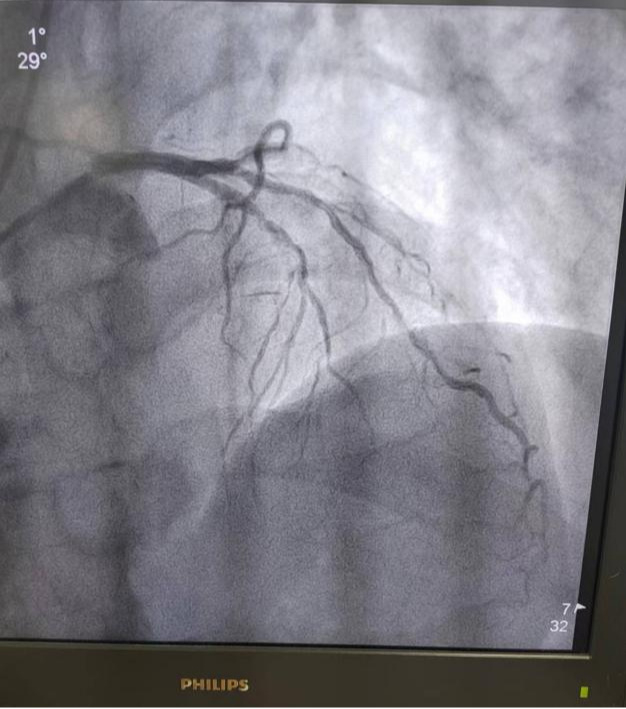

血管钙化是补钙闹的?患有骨质疏松、一直在吃钙片的张阿姨,前阵子又发现了冠状动脉钙化,她疑惑这血管钙化是不是补钙引起的,以后还能不能继续吃钙片。血管钙化的成因难道是补钙补多了?今天,就给大家详细介绍一下这个病的来龙去脉,让补钙不纠结。 血管为什么会钙化 钙化本质上是各种来源的钙在炎...